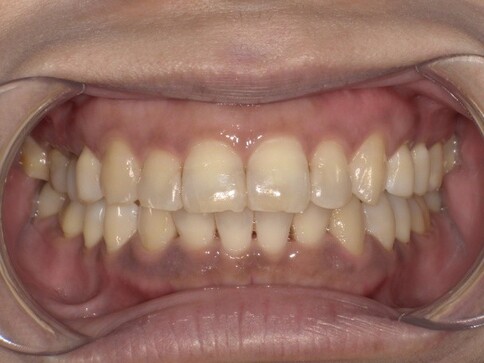

當您只有「單顆」門牙受損時,挑戰在於模仿隔壁那顆「天生的牙」。我們利用全瓷冠的高透光性創造視覺平衡,避免做出一顆看起來很新卻很突兀的假牙。

Case 2:下顎單顆假牙,齒質足夠支撐復型。